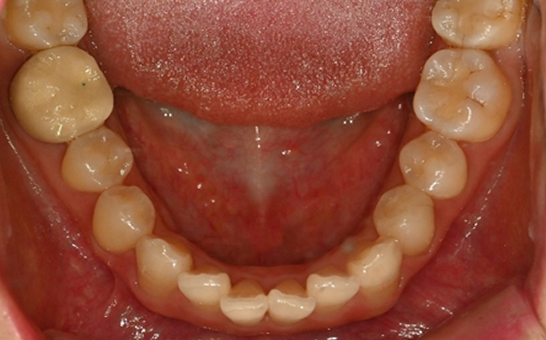

인비절라인 퍼스트(Invisalign First)는 어린이와

성장기 청소년을 위한 투명 교정 장치로, 치아와 턱뼈가

성장하는 과정에 맞춰 설계된 교정 시스템입니다.

해당하는 증상이 있다면 전문의와 상담 후 조기 교정 시

성장기 어린이에게 교합이 틀어지는것을 미리 예방 할 수 있습니다.

영구치가 나오는 과정에서

공간이 부족한 어린이

앞니의 심한 돌출이나

비대칭으로 인한 기능적

문제가 있는 어린이

※ 바른선택치과의원은 의료법을 준수하며 위 케이스는 실제 내원 환자분의 동의하에 공개된 사진과 동일한 환자분께 같은 조건에서 촬영한 사진을 활용했습니다.

개인에 따라 진료 및 치료 방법이 다르게 적용할 수 있으며, 효과와 부작용이 개인마다 다르게 나타날 수 있는 점을 안내해 드리며, 진료 전 전문의료진과 충분한 상담을 권해드립니다.